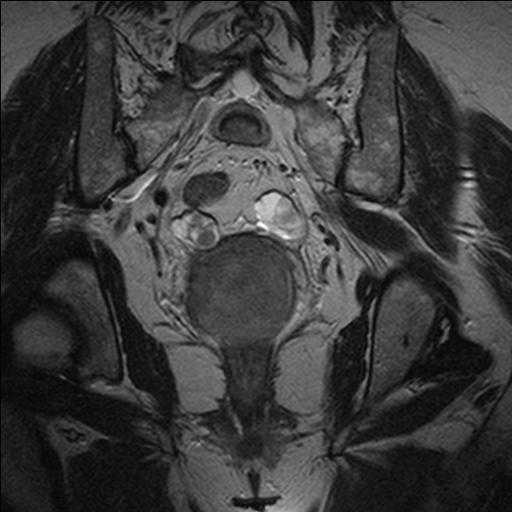

КТ диагностика тубоовариального абсцесса: Подходы и изображения

Раздел: Объективный взгляд